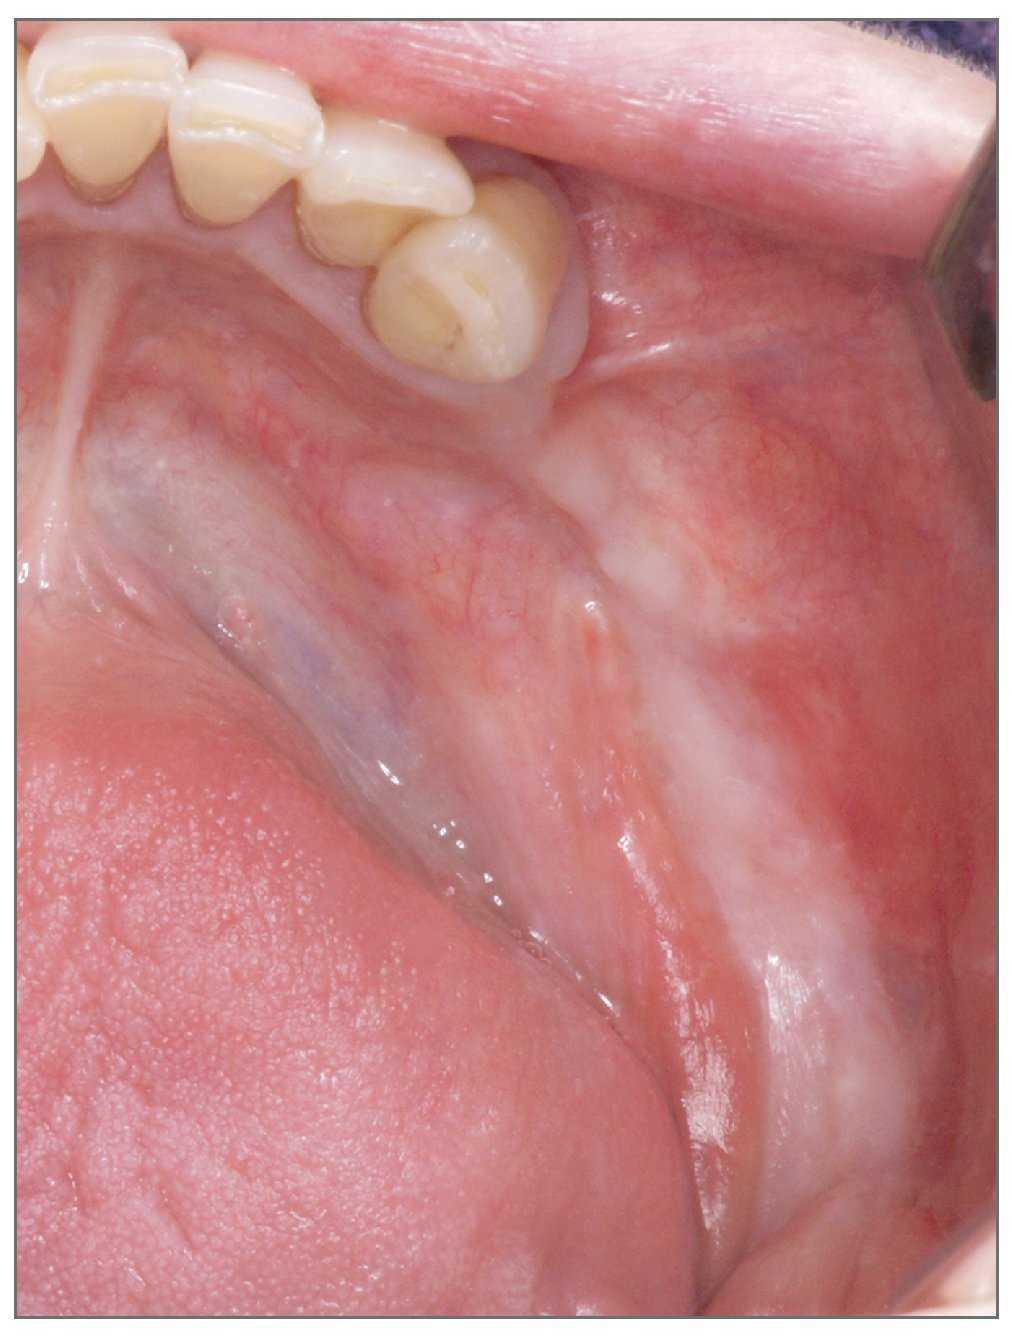

Después de la secuestrotomía, la paciente experimentó una exposición ósea continua tanto en maxilar como en mandíbula. Para tratar la exposición ósea, como primera elección, se le administró tratamiento conservador. El tratamiento conservador curó con éxito la exposición ósea del maxilar pero no así la de la mandíbula. Se realizó una resección marginal en la mandíbula derecha, pero de nuevo se desarrolló osteonecrosis con supuración persistente sobre una mucosa no cicatrizada (figs. 2 y 3). Debido al estado general de la paciente pareció inadecuado recurrir a un tratamiento más radical. Por ello, se realizó sólo un desbridamiento conservador que incluyó la resección del hueso necrótico.

Figura 2 (derecha). Recidiva de la osteonecrosis de la mandíbula.